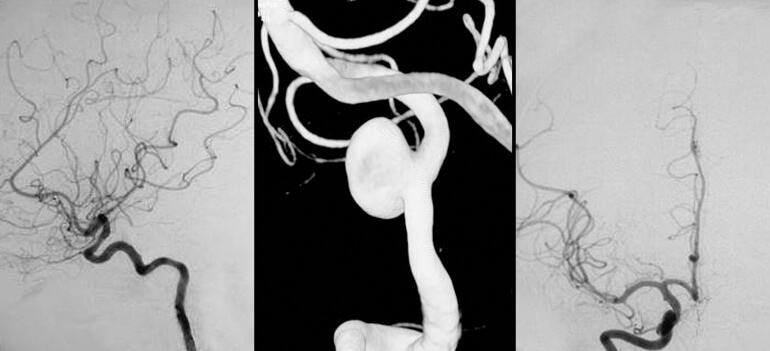

A angiografia digital é considerada o padrão-ouro para no estudo da árvore arterial e venosa cervical e intracraniana. Entre as principais patologias onde a angiografia cerebral contribui com informações relevantes estão as hemorragias intracranianas, acidentes vasculares isquêmicos e tumores cervicais e intracranianos.

Além de sua utilidade diagnóstica, a angiografia cerebral é o método de imagem utilizado nos procedimentos terapêuticos neurointervencionistas.